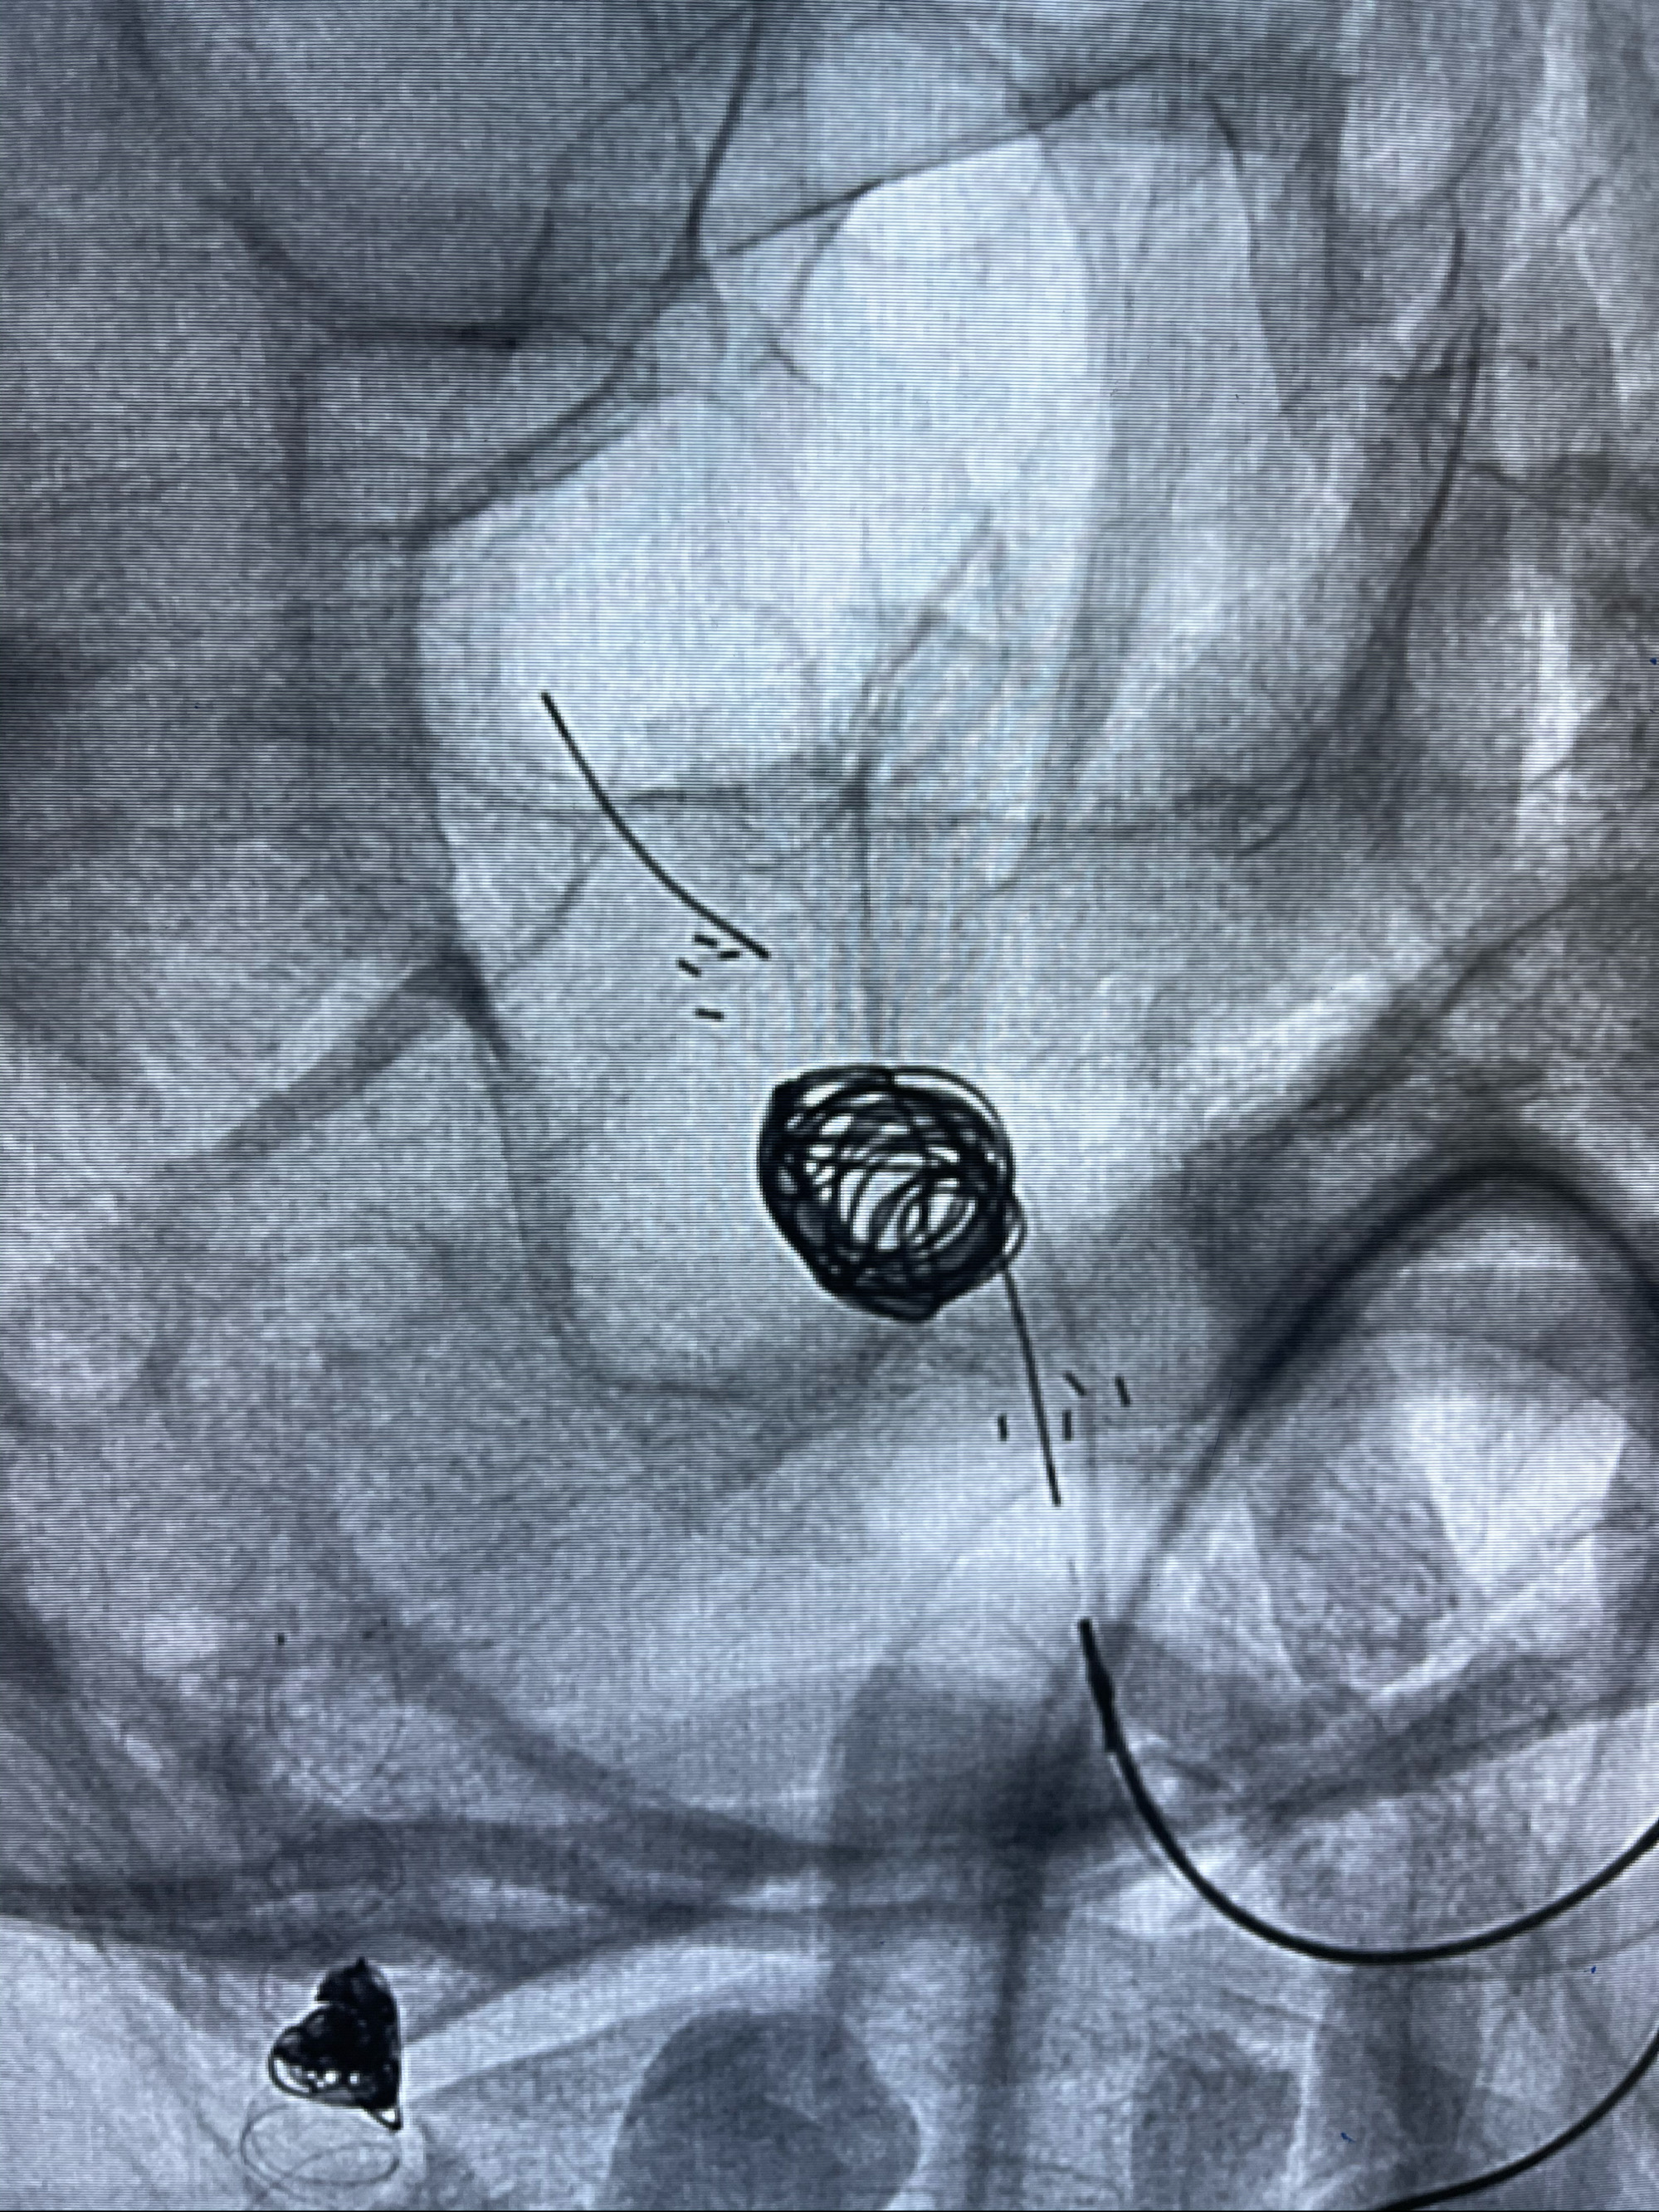

支架释放,透视下

麻醉苏醒佳,遵嘱动作。